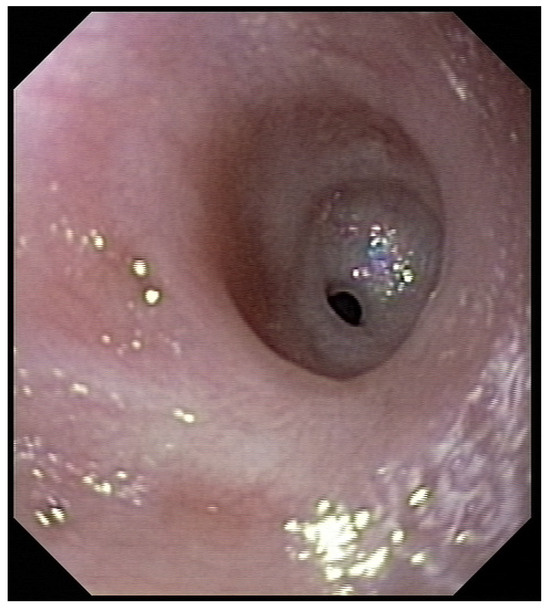

Three weeks before surgery, the children were transferred from Africa to Switzerland for the evaluation of their nutrition status, as they eventually needed to be fed carefully and progressively. A thoracic X-ray and an esophagogram are performed (Figure 2). Intubation allowed an endoscopic evaluation of the grade of esophageal and pharyngeal stenosis and mobility of the vocal cords (Figure 3). This evaluation was done with our ear nose and throat (ENT) colleagues, and eventual tracheotomy was discussed for very high stenosis of the larynx without residual damage to the esophagus.

Figure 3. Preoperative endoscopic evaluation to assess the grade of esophageal stenosis.